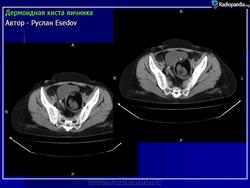

Дермоидная киста